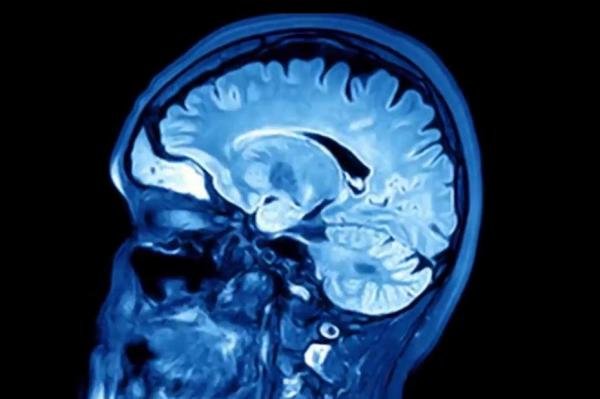

زوال عقل به اندازه ایدز برای سلامت جهان تهدیدکننده است

متخصصان سلامت در "مجمع شورای جهانی زوال عقل" تاکید کردند که زوال عقل به اندازه ویروس HIV و بیماری ایدز تهدیدی جدی برای سلامت عمومی به حساب می‌آید.

به گزارش ایسنا، وزیر سلامت هلند در سخنرانی خود در مجمع شورای جهانی زوال عقل که در ژاپن برگزار شد، گفت: زوال عقل همچون بیماری ایدز و ویروس HIV تهدیدی جدی برای سلامت جهانی به حساب می‌آید و تعداد مبتلایان به این بیماری تا سال ۲۰۳۰ به جمعیت آلمان نزدیک می‌شود.

به گفته وزیر سلامت هلند، بیماری زوال عقل به خوبی شناخته نشده و مورد غفلت قرار گرفته است و همانطور که در سال‌های نخست شناسایی بیماری ایدز و ویروس HIV این وضعیت وجود داشت.

اکنون در آستانه همه‌گیری بیماری دیگری هستیم؛ بیماری که سیستم ایمنی بدن را هدف قرار نمی‌دهد بلکه مغز، حافظه و شخصیت انسان را تهدید می‌کند.

به گزارش روزنامه گاردین، وزیر سلامت هلند افزود: هزینه مراقبت‌های مربوط به بیماران مبتلا به زوال عقل در سال ۲۰۳۰ حدود دو تریلیون دلار خواهد بود. بدون شک زوال عقل یکی ازبزرگترین چالش‌های اجتماعی و پزشکی است که بشر در سال‌های پیش‌رو با آن روبرو خواهد بود و در برخی از کشورها این بیماری عامل اصلی مرگ و میر به حساب خواهد آمد.